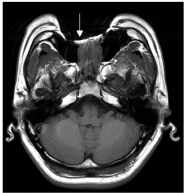

44.下圖為磁振影像,箭號所指為何種現象引起?

(A)化學位移(chemical shift) (B)截斷(truncation) (C)移動(motion) (D)串擾(cross-talk)